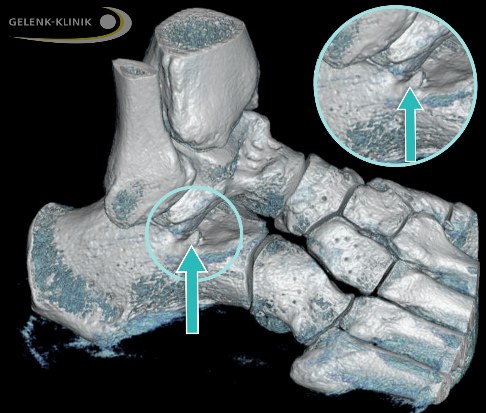

Evans-Osteotomie: Fußbegradigung durch knöcherne Korrektur

Ziel dieses Eingriffes ist es, den Fuß zu begradigen. Um eine Chance auf eine langfristige Korrektur zu haben, müssen die Zugverhältnisse und Weichteilspannungen der Fußwurzel verändert werden. Der Weichteileingriff an der Tibialis-posterior-Sehne kann dies praktisch nie alleine erreichen. Über einen Schnitt im äußeren Bereich des Fersenbeins (Calcaneus) bringt der Arzt einen Knochenkeil z. B. aus dem Beckenkamm ein. Diese Operation korrigiert die Stellung von Vor- und Mittelfuß gegenüber dem Sprungbein (Talus).

- Beim Verlängerungseingriff eröffnet der Arzt die Gelenkkapsel. Nach Spreizung entfernt er den geschädigten Gelenkknorpel und bringt einen festen Knochenspan ein. Dieser ist erfahrungsgemäß 1 bis 1,5 cm lang. Anschließend befestigt der Orthopäde den Knochenspan mit einem Draht oder einer Metallplatte, um eine sichere Überbrückung und Ausheilung zu erreichen.

- Bei intaktem Gelenk und guten Knochenverhältnissen wird der Fersenbeinknochen etwa 1 cm hinter dem Gelenk mit dem Meißel durchtrennt. Daraufhin erfolgt die Spreizung und der Einsatz des Knochens.